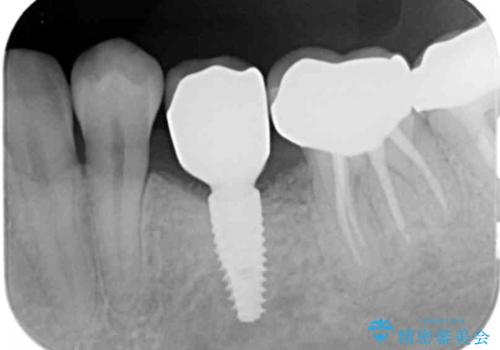

- 残していた乳歯がぐらつき始め、抜去ののちのインプラント治療を希望され来院されました。

乳歯を抜去して歯ぐきの状態が落ち着いたのち、骨の増成を伴うインプラント治療を行い機能の回復を図ります。

生まれつき永久歯の欠損がある場合、乳歯が大人になっても残っている場合があります。

残念ながらぐらつきが大きくなり、残すことが難しくなり抜去したのちインプラントを用いて咬合機能の回復をしっかりと行いました。